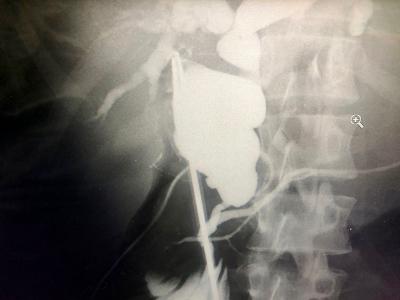

Se trata de un paciente que ingresó al centro asistencial con la piel de un color amarillento, esto debido a una acumulación de bilis en su cuerpo, se le realizó todos los estudios médicos y se diagnóstico una dilatación quística del colédoco, que es la dilatación de la vía biliar intra y extra hepática y es provocada por una anomalía en la anatomía del cuerpo.

El paciente requirió de una cirugía laparoscópica, la primera que realiza el Hospital General San Juan de Dios. Este es un procedimiento que usa el médico para observar el interior del abdomen y la pelvis. Se hace con un lente de laparoscopia, una fuente de luz y una cámara de video.

La enfermedad por la que el paciente requirió una cirugía laparoscópica afecta más a mujeres y regularmente, estos casos se diagnostican en la niñez y cuando se detectan en adultos son hallazgos incidentales entre los 20 y 30 años de edad. Para diagnosticarlos se realiza un estudio de colangioresonancia o una tomografía.